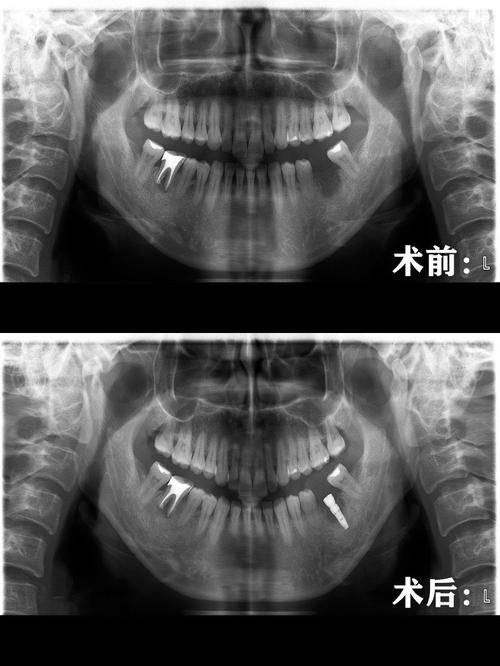

3. 杆卡式种植覆盖义齿:欧忠辉医生擅长杆卡式种植覆盖义齿技术。这种技术适用于牙齿缺失较多的患者,通过种植体与义齿的连接,提高义齿的稳定性和咀嚼功能。欧医生在手术过程中,能够精细地植入种植体,确保义齿的贴合度和舒适度。同时,他还会根据患者的口腔情况和生活习惯,为患者提供个性化的义齿设计,让患者能够更好地适应义齿。

3. 患者王先生,牙齿缺失多年,一直佩戴活动假牙,但佩戴成效不佳,咀嚼功能也受到了较大影响。他找到欧忠辉医生,希望通过种植牙来修复牙齿功能。欧医生为王先生进行了详细的口腔检查和评估,制定了杆卡式种植覆盖义齿的治疗方案。手术过程非常顺利,欧医生精细地植入了种植体,并为王先生安装了合适的义齿。术后,王先生的咀嚼功能得到了明显改善,义齿的稳定性也良好。王先生评价说:“欧医生的种植牙技术非常厉害,让我重新拥有了健康的牙齿。手术过程中我没有感觉到太多的疼痛,术后修复也特别快。现在我可以像正常人一样吃东西了,真的太感谢欧医生了。”